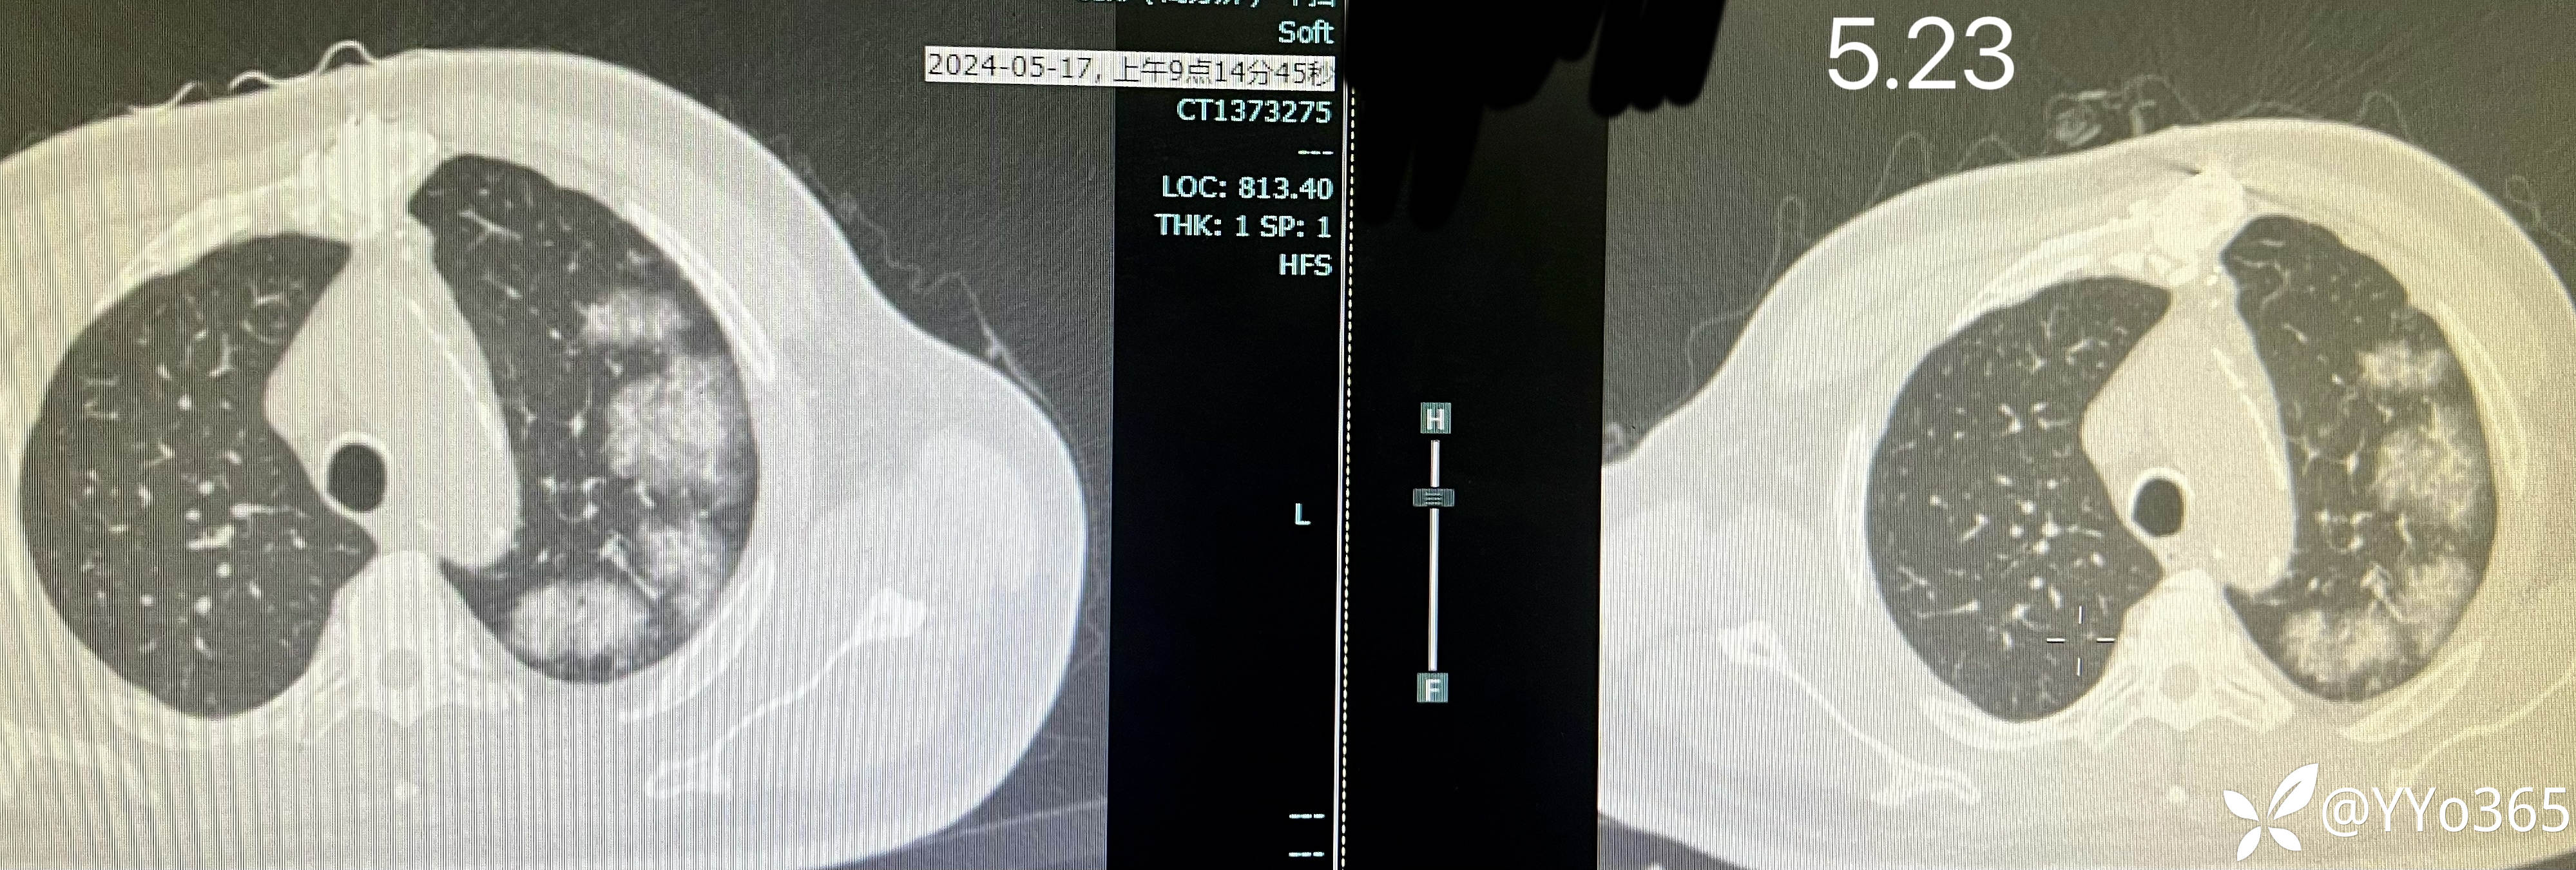

5.23复查ct,肺部影像吸收不明显

以下是治疗前后对比图